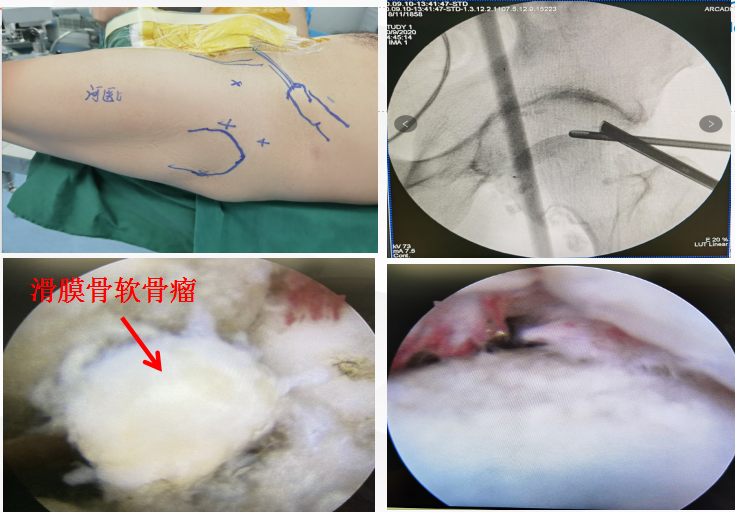

手术中髋关节病变部位

而髋关节镜手术的出现让患者担心的问题迎刃而解。髋关节镜手术是一种微创手术,由于髋部解剖结构复杂,所以这类手术虽然操作复杂难度大,但是由于使用关节镜通过2-3个不足1CM的皮肤切口,对关节疾病进行诊断与治疗,与传统切开手术长12CM左右的切口相比具有伤口小、出血少、疼痛轻及术后恢复快的特点。

经过科室专家们的详细讨论,为了让患者得到及时有效的治疗,决定给患者在硬膜外麻下行左侧髋关节镜手术治疗。随后,与患者及家属进行充分沟通后,在科室专家的带领下,医护团队共同为患者进行手术,手术过程顺利。本次手术创伤小,出血少,几乎不损伤髋关节周围的相关结构,并发症低,术后恢复快,住院日短,患者现已康复出院!